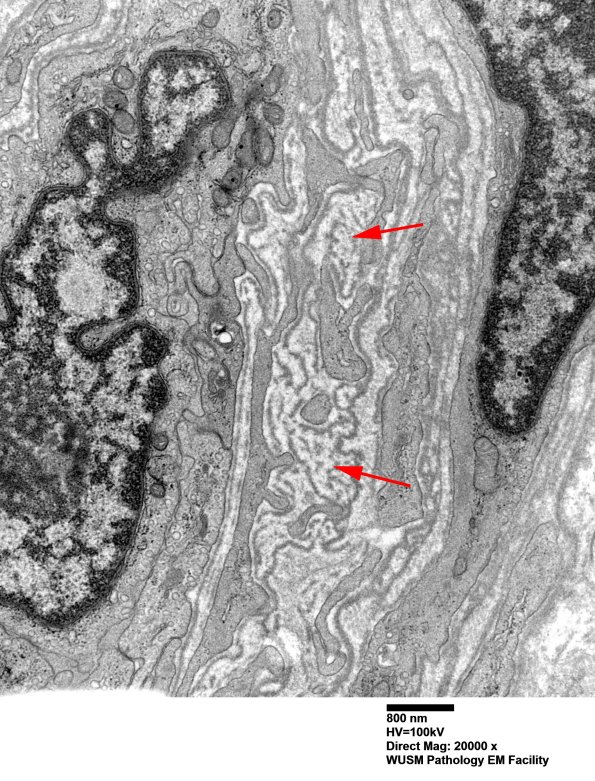

There are numerous fragments of basal membranes (arrows, 16B8) within the abnormal vessel wall. (electron micrographs)